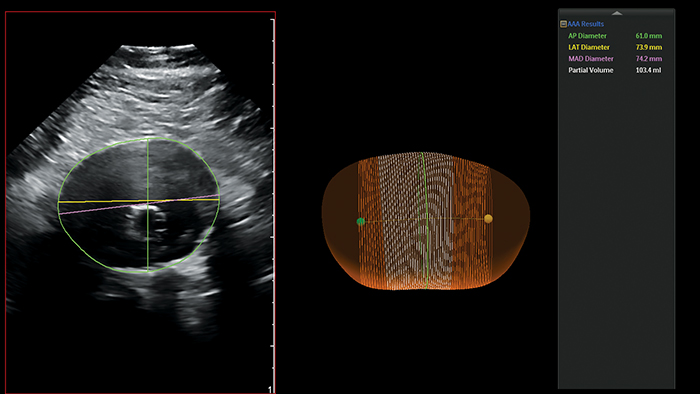

フィリップスの腹部大動脈瘤(AAA)モデルは、動脈瘤の中心線を示し、最大前後(AP)径や部分容積などの主要測定値を提供します。

AAA の最大径は中心線に垂直に測定するのが理想とされていますが、これまでそれが可能なのは 3D CT および磁気共鳴血管造影法(MRA)のみでした⁵。フィリップスの AAA モデルは、ボリュームデータ全体を通して AAA の中心線を示すことにより、この方法を 3D 超音波検査でも可能にしました。

また、フィリップス AAA モデルは動脈瘤の部分容積も示します。これが有用なのは、直径のみでは安定していると考えられていた小さな動脈瘤の 1/3 超で、実際には容積増加が観察されているためです⁶。